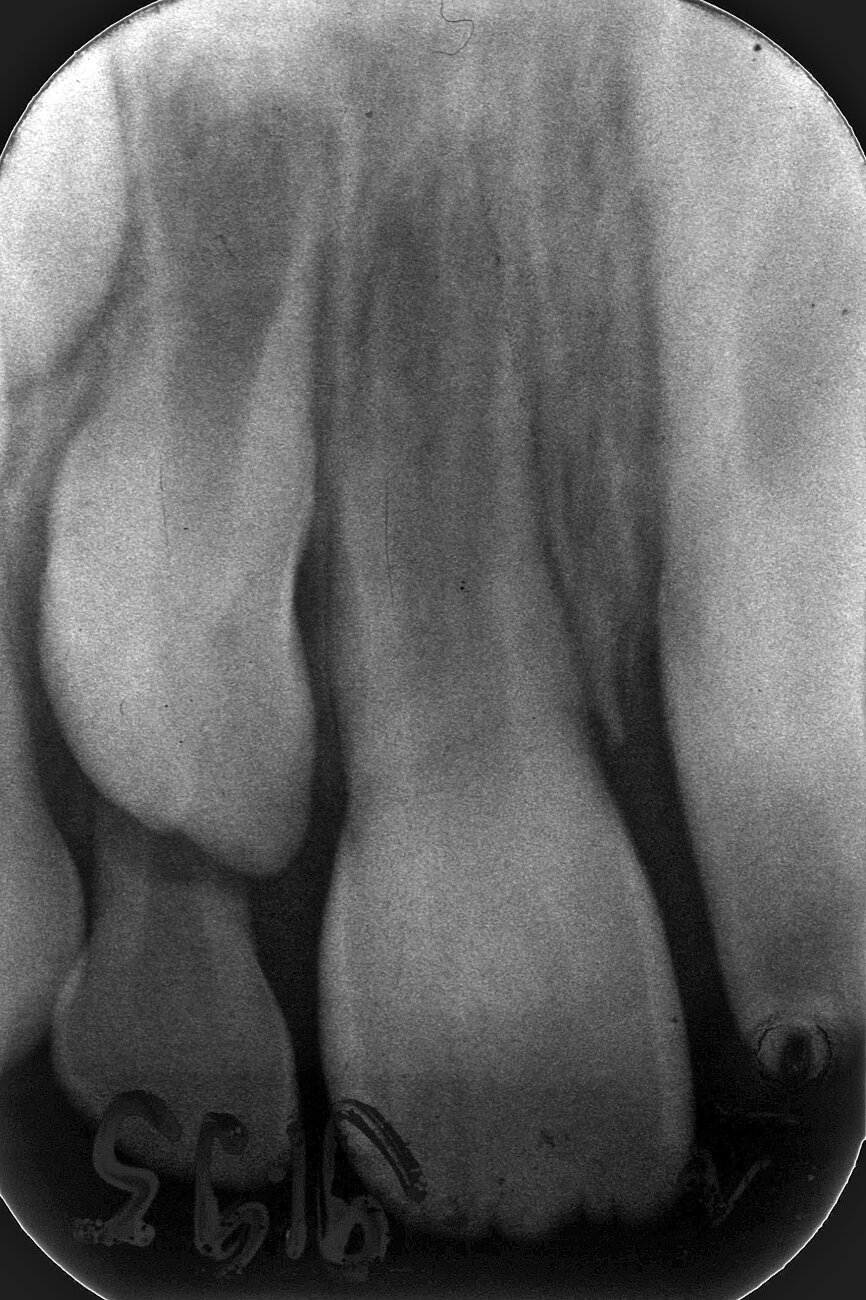

Case 3: Female (born 8 August 1988): Tooth 11

Fig. 5a: 4 September 1995 ante RCF

(non-vital).

Fig. 5b: 4 September 1995 post RCF

Fig. 5c: 22 April 2002 status.